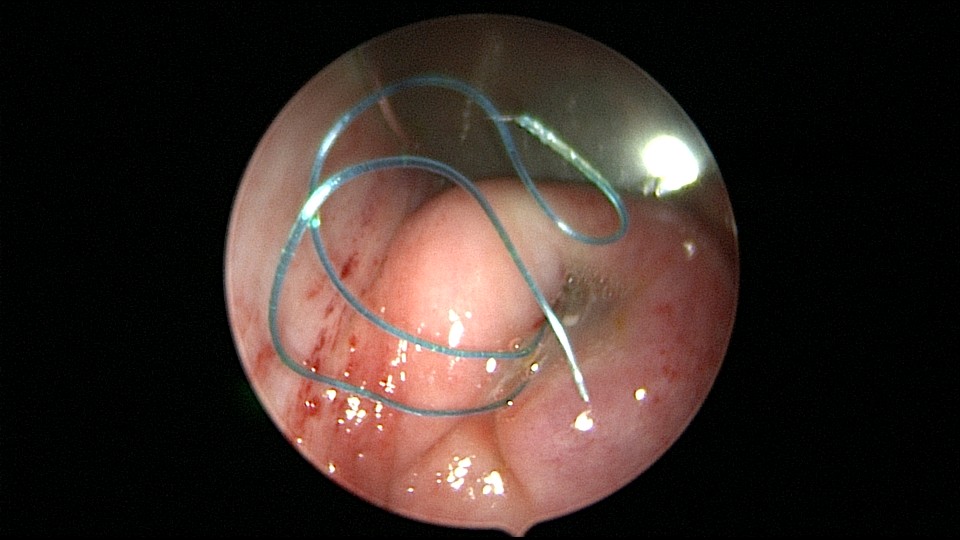

患者56岁,G3P1,顺产1次。安环20+年,绝经10年,下腹坠胀不适1周,B超提示子宫后位,宫内无回声区2.4cm×1.5cm。宫颈外口见节育环尾丝,环纵臂卡在宫颈管内,宫腔镜难以进入宫腔,取环后看到宫腔粘稠白色脓液,宫腔左侧前后壁粘连,膨宫液冲洗脓液,宫腔无其他异常。